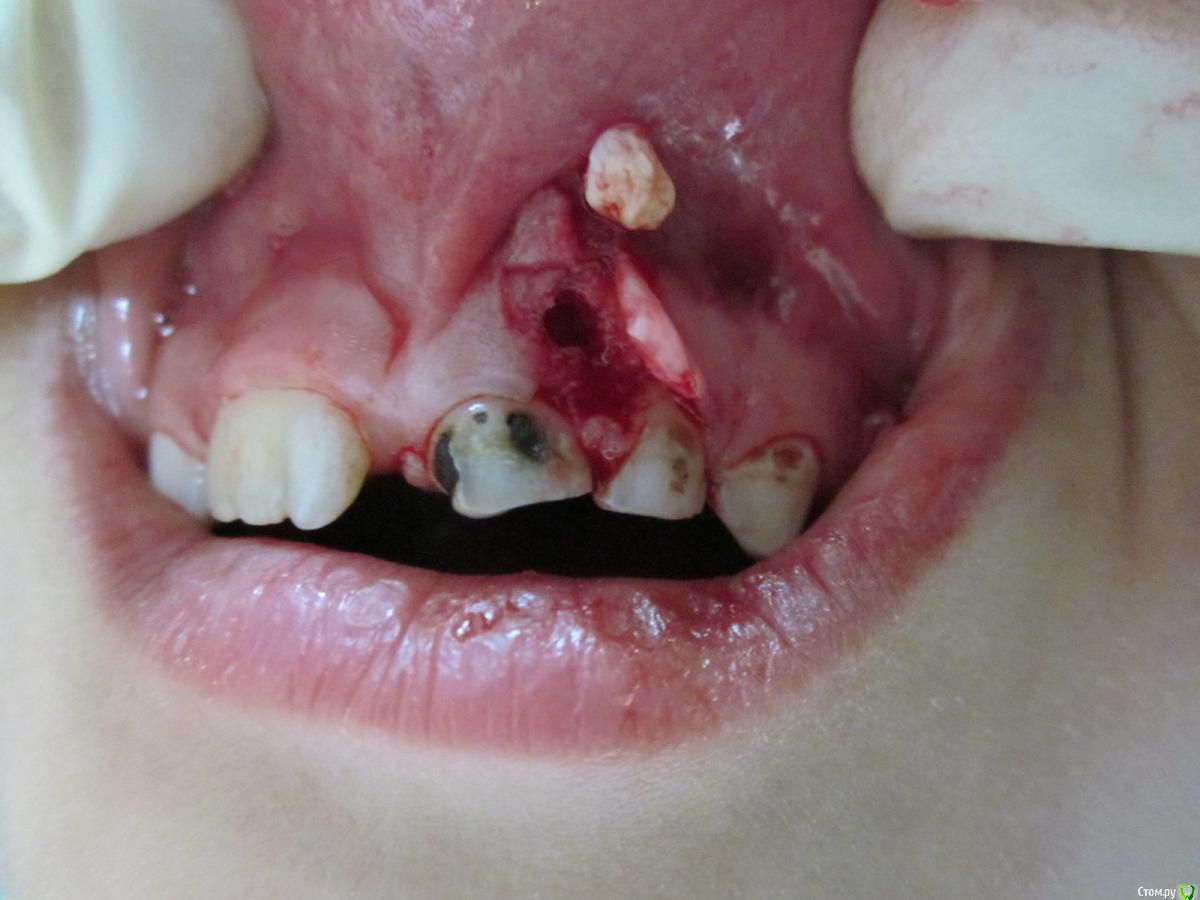

По данному случаю: пациент 6-7 лет, 21 не растёт, все динамят (ортодонты и терапевты), дошли до хирурга: на снимок прицельный, что то не то, на КТ охарактеризовал как одонтому. Операция под

анестезией Ультракаин дс, кортикальную пластинку трепанировал «расковырял» эскаватором, убрал конгломерат тведых тканей, саму оболочку, удалил 61. Биологический материал в пробирку с физ

раствором, направление на исследование в гистологию и ГОУ самим.